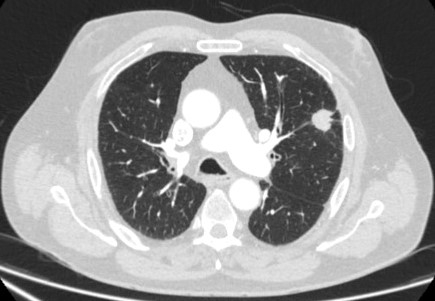

Tomografia computadorizada (TC) mostrando duas áreas (círculos vermelhos) de impactação mucoide dos brônquios subsegmentares do lobo superior esquerdo, resultando em aparência que mimetiza um nódulo

Do acervo de Dr. George Tsaknis, MD, PhD, FRCP (Londres), MRQA, MAcadMEd, PGCert; usado com permissão